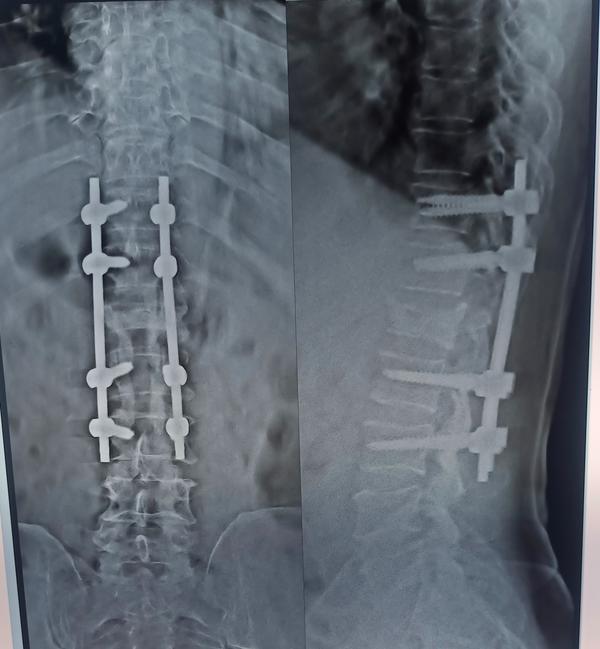

SPINE FIXATION WITH DECOMPRESSION DISCECTOMY IS TH...

View Details